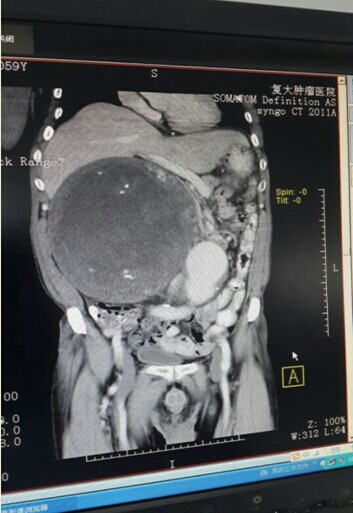

几经波折,刘x恩终于来到了徐院长的面前,徐院长看过病人后随即将病人的CT片给我院手术外科专家李朝龙教授过目,李教授看后满怀信心的说:“先做活检查病理后手术,我来做。手术费用在8-9万。”看到老教授如此满怀信心,而且费用比之前的要少三分之二,刘x恩一家决定尝试。然而活检取出的囊性组织均坏死,无法得出病理结论。在两次病理均无果的情况下,李教授决定立即手术,术后做病理。2014年6月26日经过4个多小时的奋战,刘x恩的肿瘤被完整拿下,肿瘤大小25*24*23.5cm,出血量仅有600ml。术后病理提示:病变符合(腹腔)平滑肌瘤。

刘x恩术前

刘x恩术前CT报告(肿瘤靠近腹腔动脉瘤)